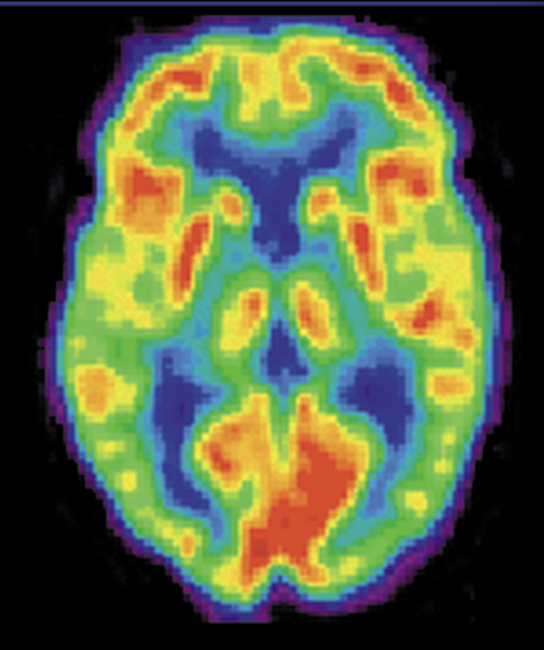

Positron emission tomography (PET)

High resolution of the brain is obtained

Radioactive chemicals (marker) injected into the blood

Relationship between the density signal of that marker and the blood flow in that area

Color of the image indicates the level of activity

RED most active, followed by yellow, green, blue for least active

Involves taking dose of radiation